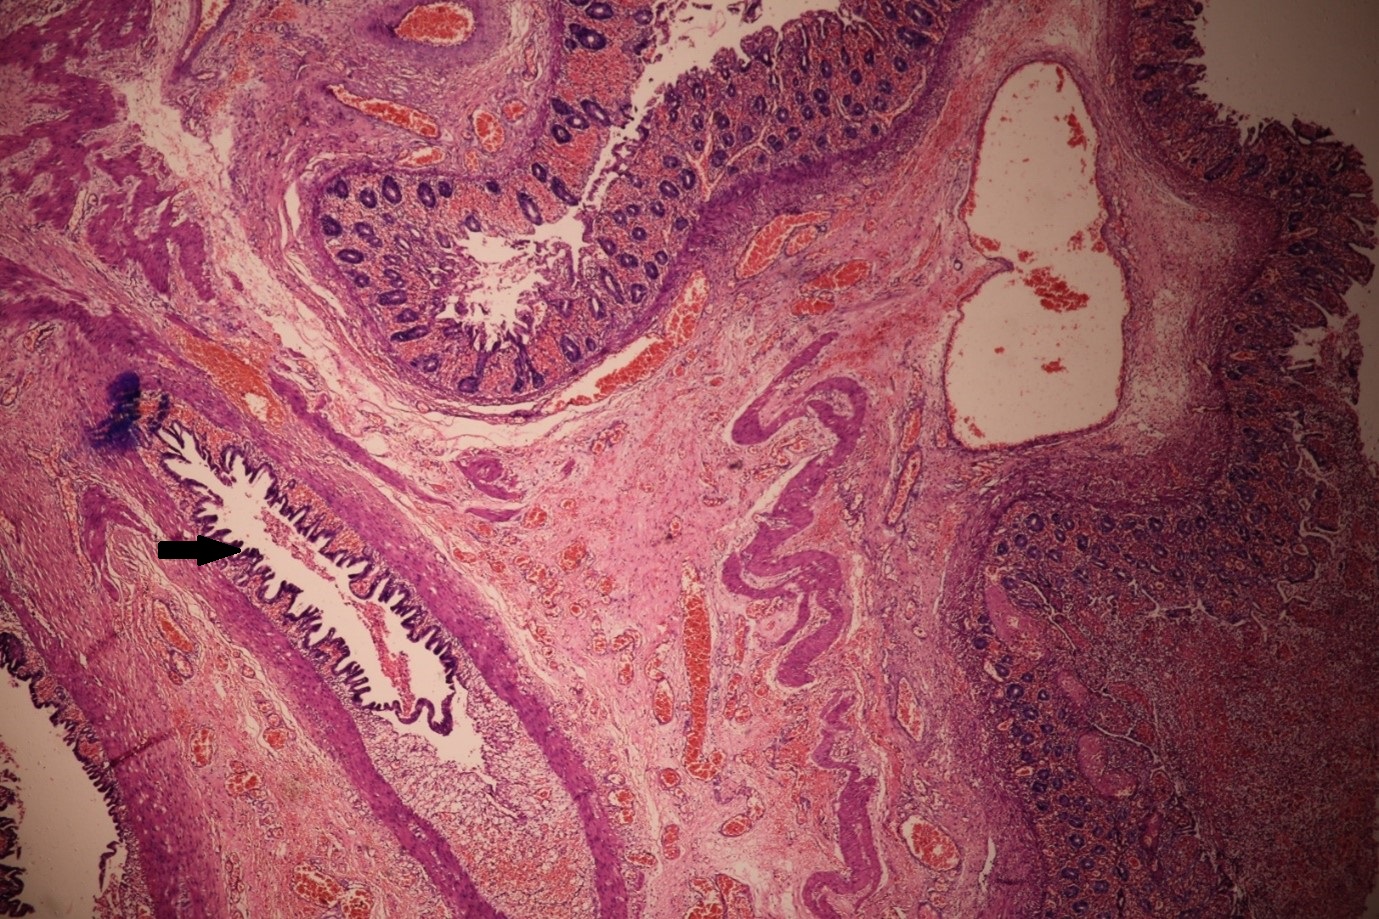

The postoperative period was uneventful, and breastfeeding was started by the 5th POD. Histopathological examination revealed cystic duplication lined by primitive epithelium suggestive of duplication cyst (Fig. 2).

Figure 2

Histopathology picture of colonic mucosa with ischemic changes. Underlying cystic duplication lined by primitive epithelium (Black arrow).